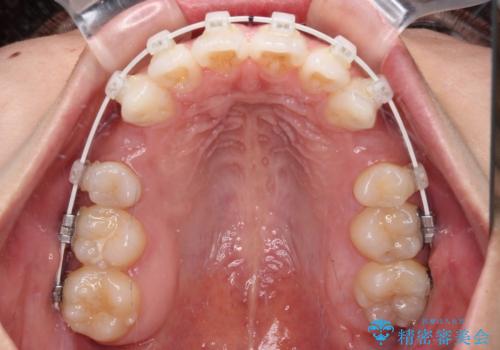

補助装置を用いて上顎歯列全体を後方に移動させ、下顎は左右で抜歯する小臼歯を変えることで、左右の咬み合わせをより理想的な位置となるように計画しました。

埋伏している右下第二大臼歯は、牽引して咬合に参加させることで計画しましたが、癒着などにより移動困難な場合には、抜歯の上インプラント補綴治療を行うこととしました。